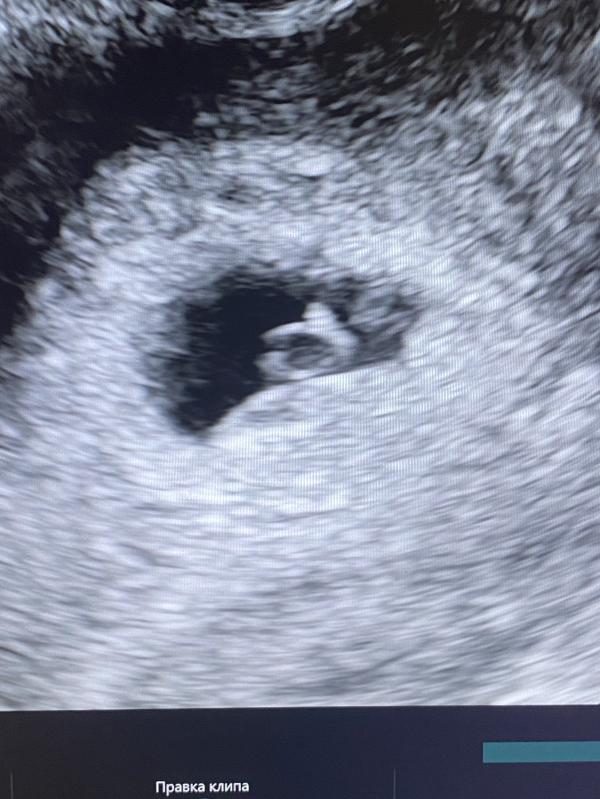

Сегодня была на первом узи. Ночь не спала. Было очень волнительно и страшно, что с малышом что-то не так. Но моя репродуктолог успокоила, сказала, что все хорошо. И плодное яйцо, и эмбриончик и даже сердечко. Все на месте. По замерам не запомнила, не до этого было. Через недельку еще раз пойду. Надеюсь, послушать сердцебиение🥹🥹🥹

Моя не давала слушать так рано) не нагружать бусинку. Мерцание видела и у колечка